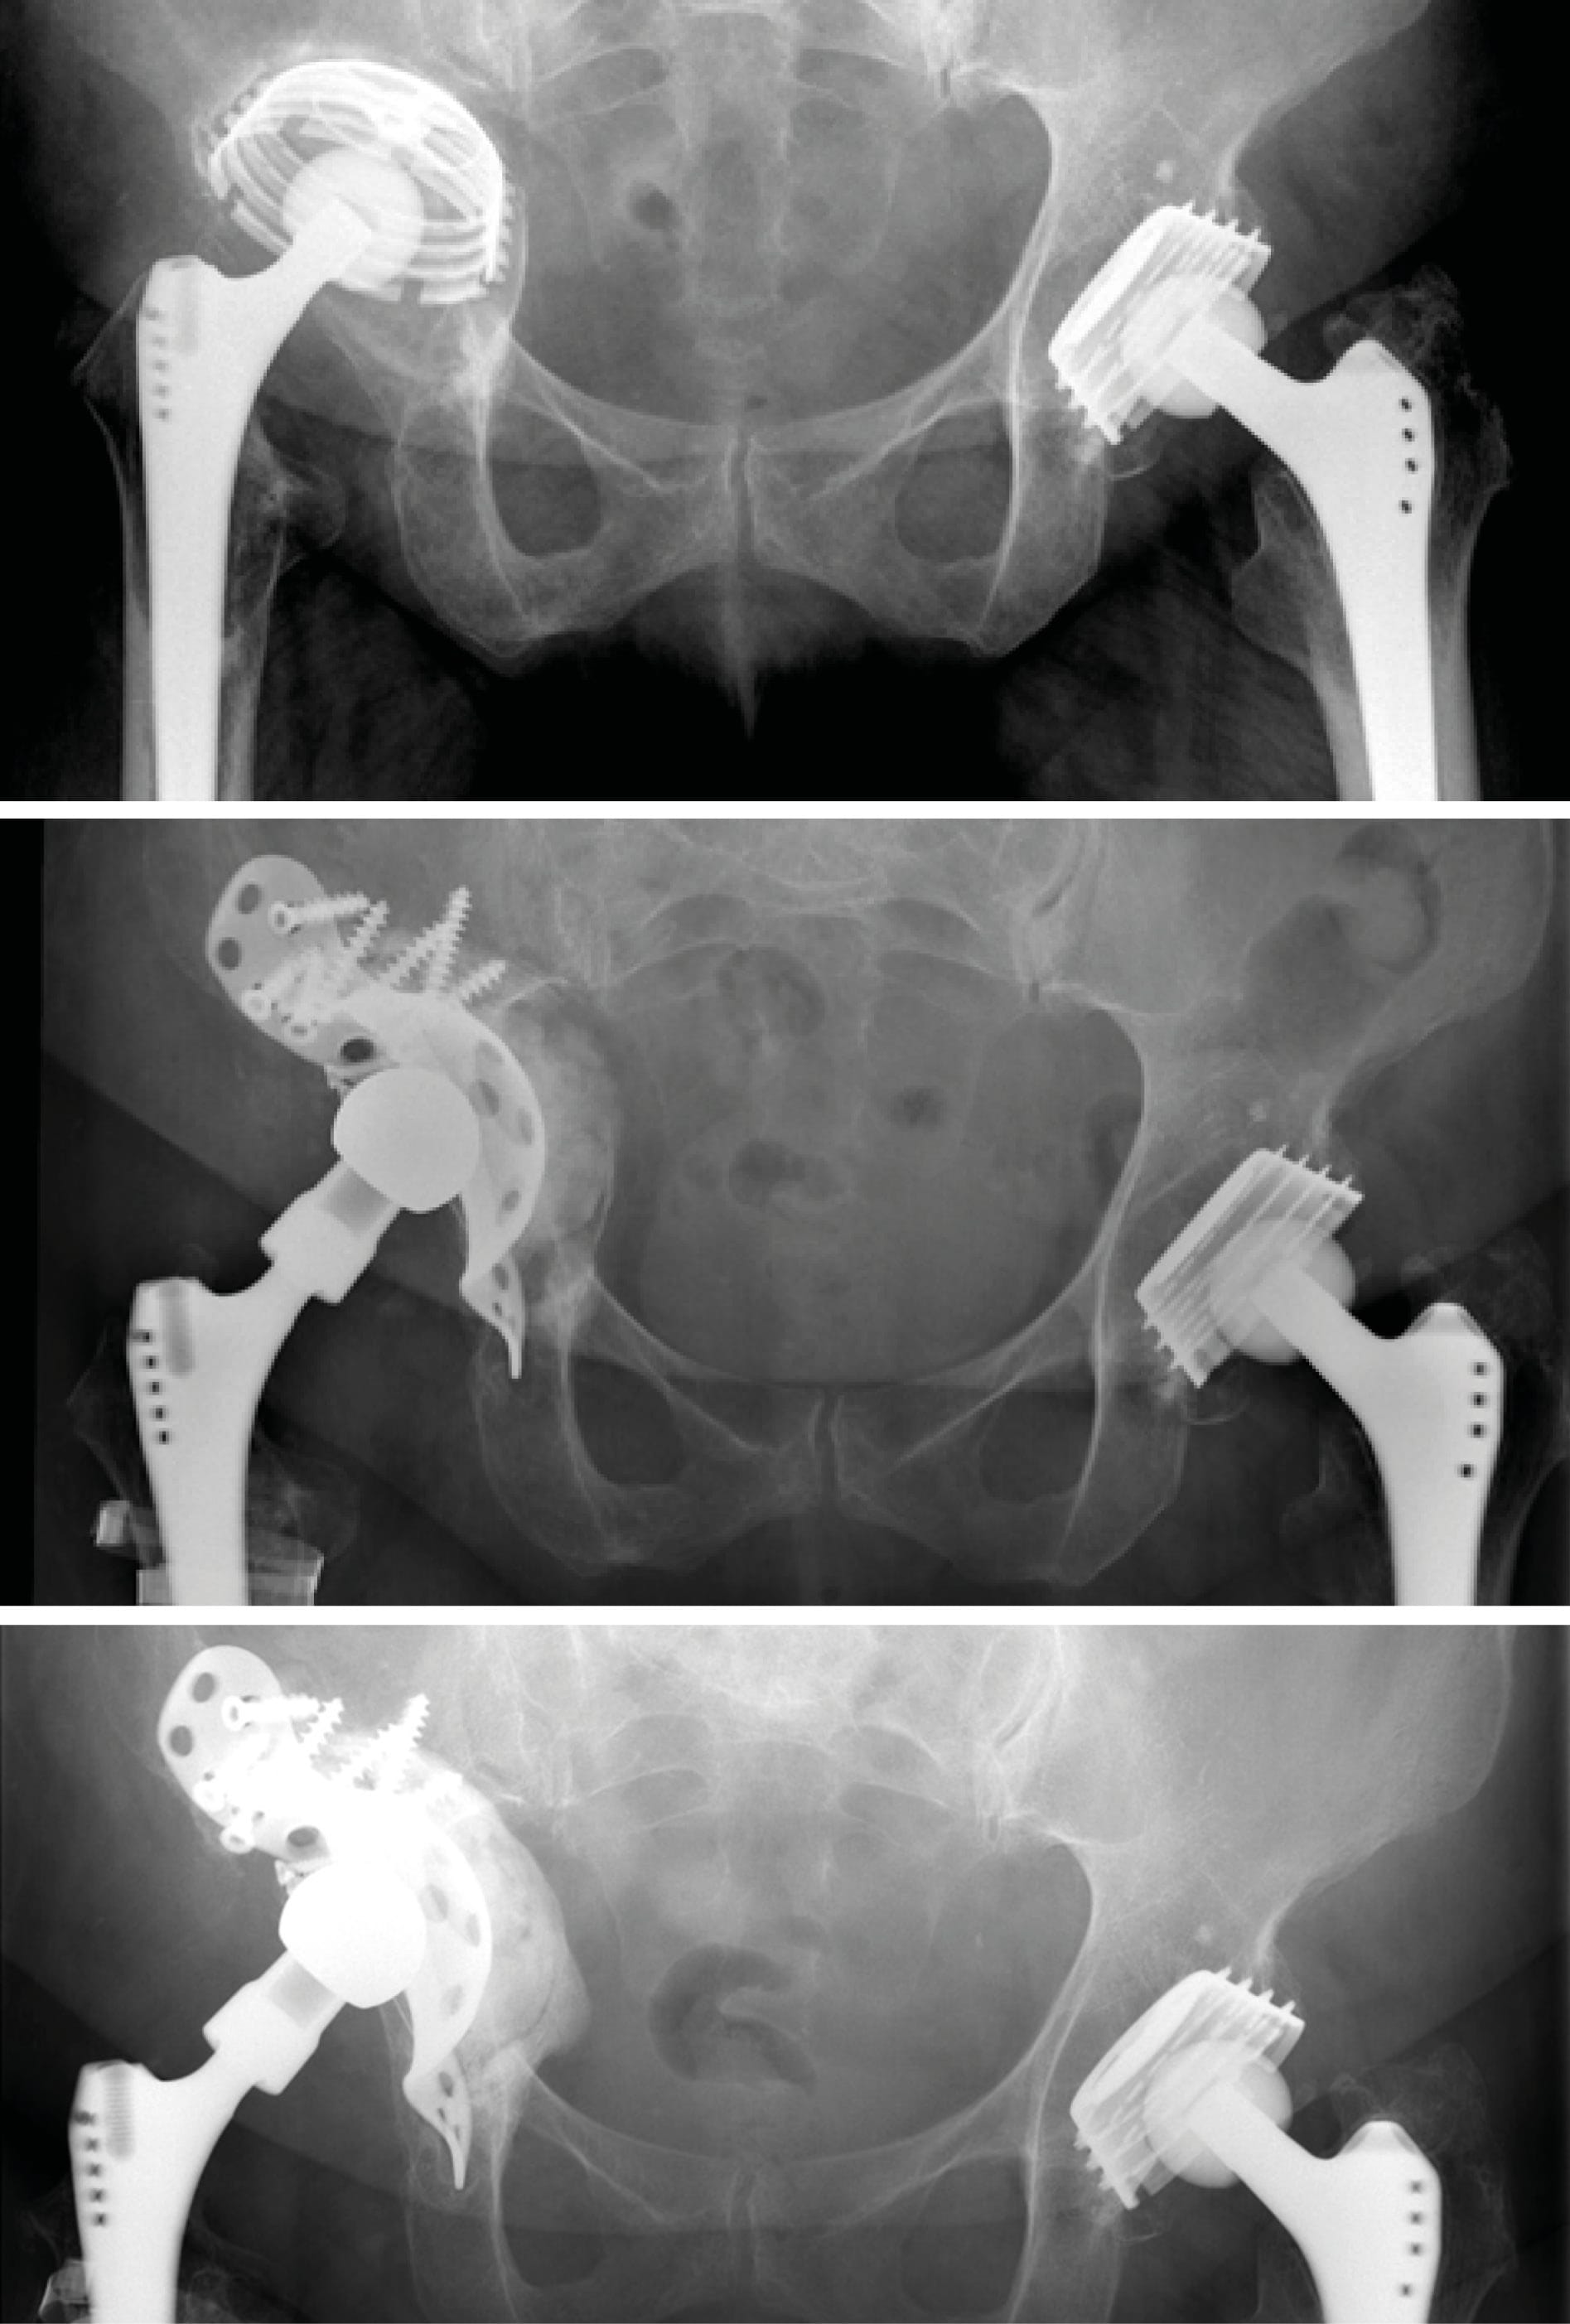

Case 3: Acetabular cup revision due to aseptic loosening (62-year-old female)

Progressive loosening and cranial migration of an uncemented threaded cup with a Paprosky type 3b (“up-and-in”) bone defect. After removal of the loose cup, reconstruction of the defect was performed with a cemented antiprotrusio cage in combination with impaction bone grafting along the medial wall. As the stem was found to be well osteointegrated, offset and neck length were restored with a Bioball® standard adapter 5XL and a ceramic head. At 10-year follow-up, radiographs showed no loosening.

Case 4: Acetabular cup revision in pelvic discontinuity (86-year-old female)

Reconstruction of pelvic discontinuity and recurrent dislocations due to medial migration of an unstable cemented reinforcement ring with an off-label application of cage and augment in combination with a cemented dual mobility cup. Neck length and offset were restored with a Bioball® standard adapter 3XL and a ceramic head.